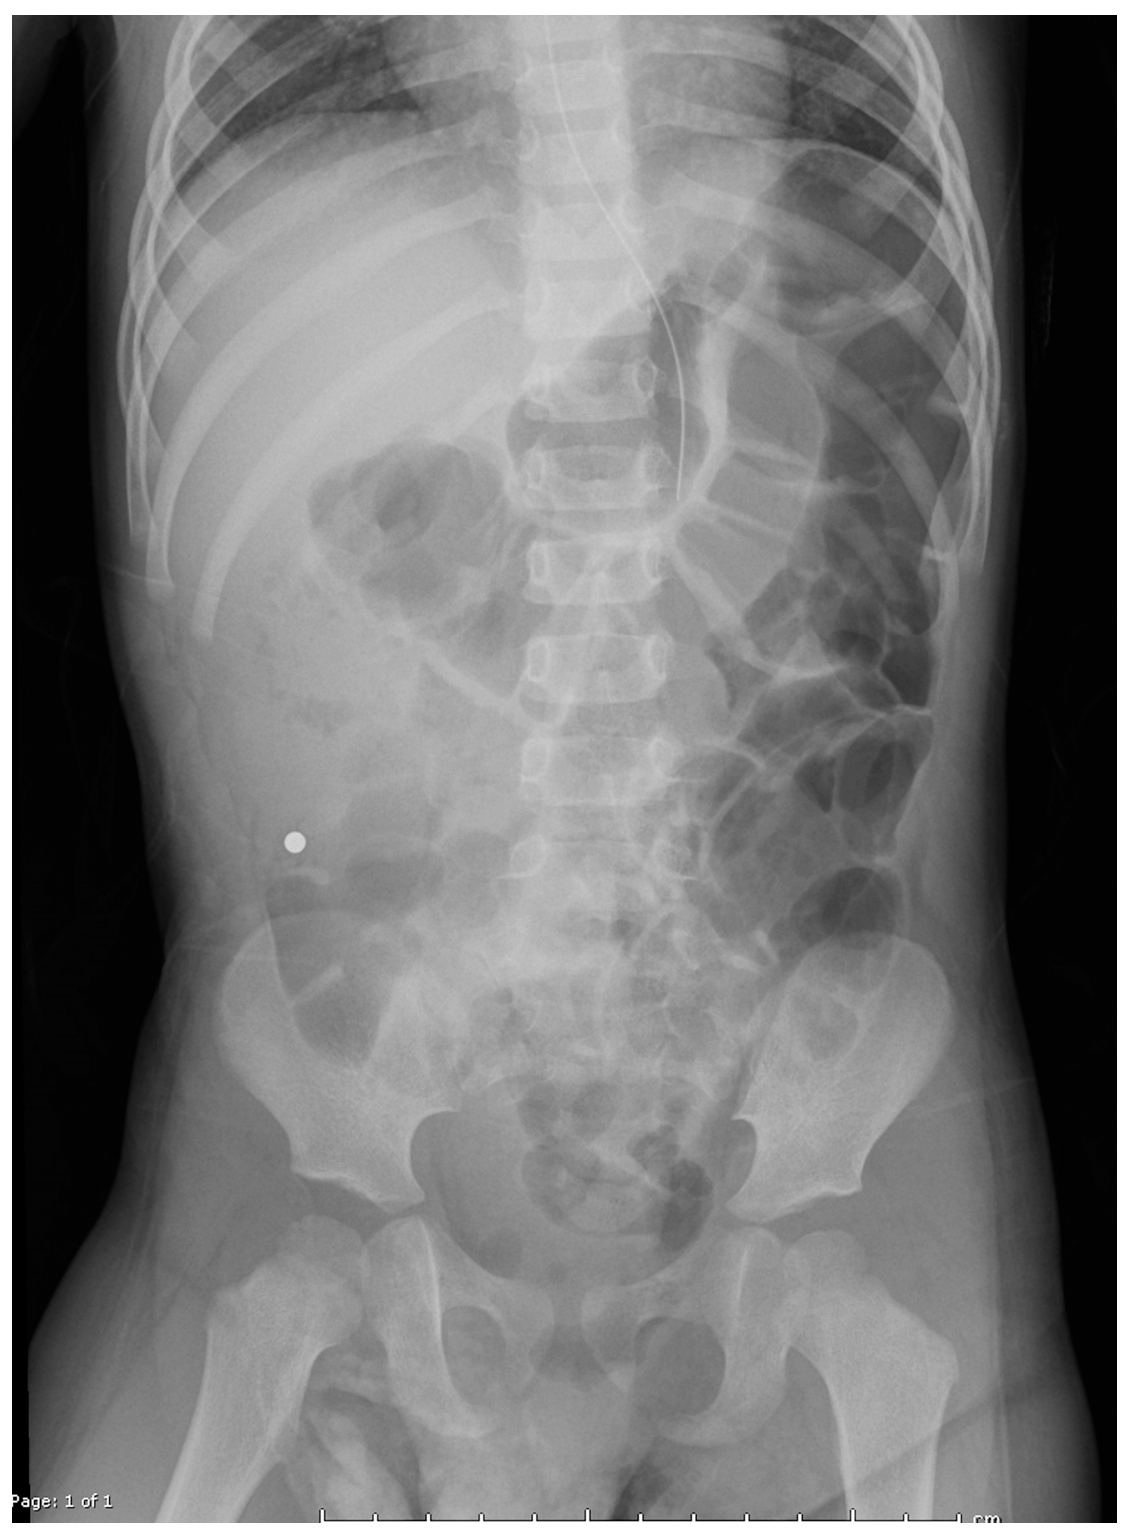

Figure 3. Post-op abdominal radiographs revealed multiple magnets remaining in the proximal jejunum.